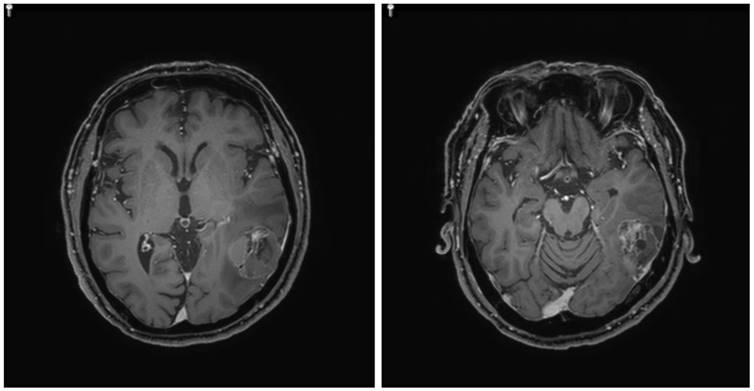

Patient. A 63-year-old man initially presented with stage III, rectosigmoid colon cancer in 2013. He underwent lower anterior resection for the primary lesion and then received eight cycles of adjuvant XELOX (capecitabine and oxaliplatin) chemotherapy. During regular surveillance, at 2015, the patient suffered from an abrupt headache. Brain imaging for the patient revealed a single brain mass. Patient received a curative intent brain surgery for the single brain mass suggesting a malignant primary brain tumor (Fig. 1). After pathologic confirmation for tumor, we generated PDCs from the patient. Finally, this resected brain lesion was confirmed in a metastatic recurrent colon cancer. NCOA4-RET fusion was detected by FusionPlex using the resected tumor sample and then reconfirmed by fluorescence in situ hybridization (FISH) test (Fig. 2). We also confirmed the RET fusions by a qPCR in matched PDCs (Fig. 3).

Figure 1

Single brain mass in magnetic resonance imaging (MRI)